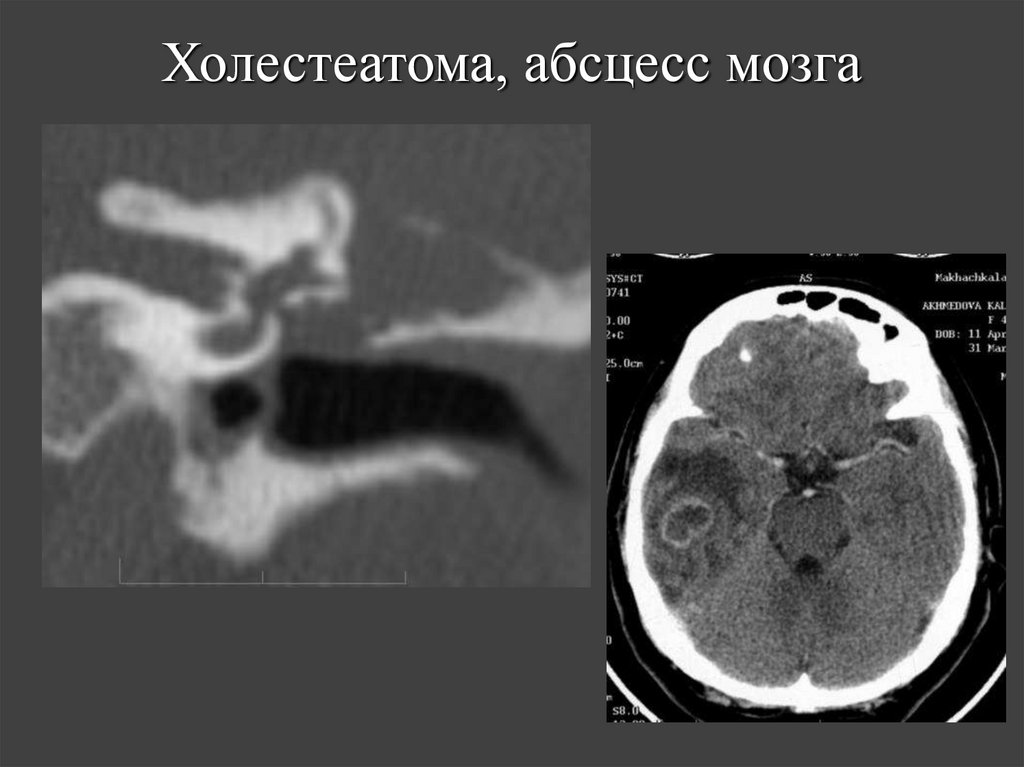

70. Холестеатома, абсцесс мозга

63. Осложнения холестеатомы, выявляемые на КТ

• Фистула лабиринта.

• Внутричерепные осложнения.